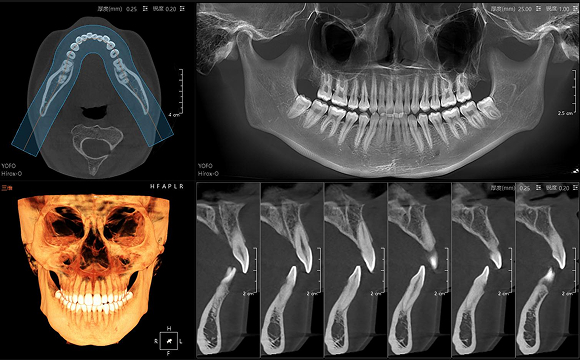

只需一次单圈扫描即可获得CT、3D全景和3D正/侧位影像,并能同时生成3D TMJ视图

提高诊疗效率,避免过度检查,减少患者所受的辐射

• CT

CT

• 3D全景

3D全景

• 3D 正侧位

3D 正侧位

• 3D TMJ视图

3D TMJ视图